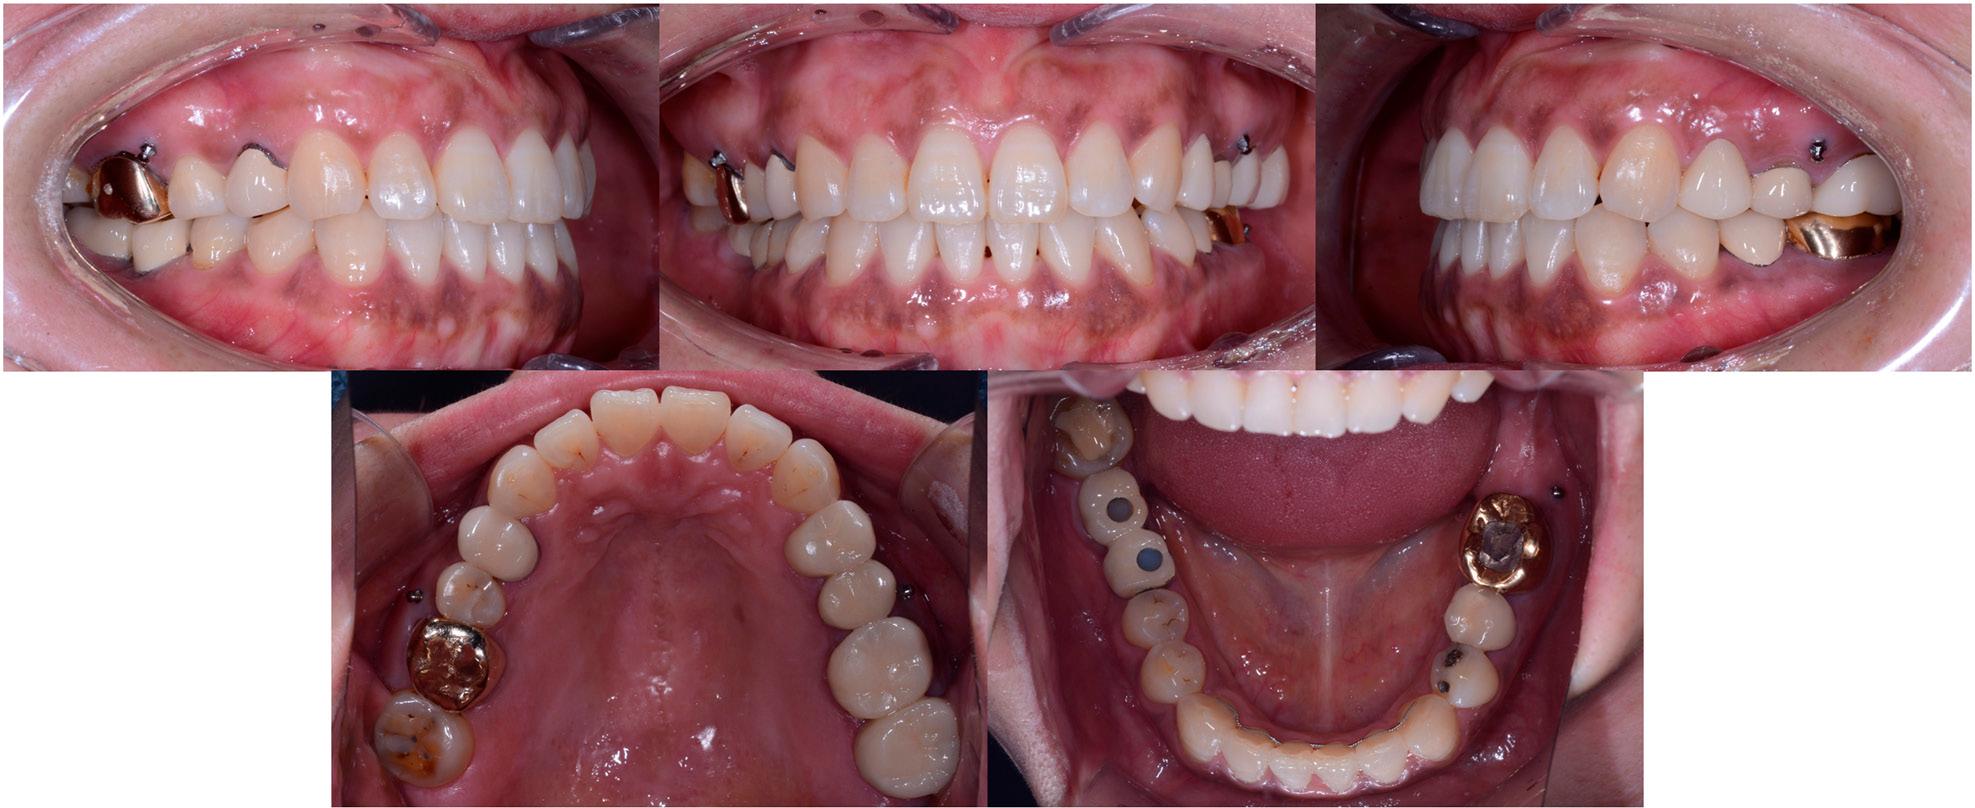

Figure 4.